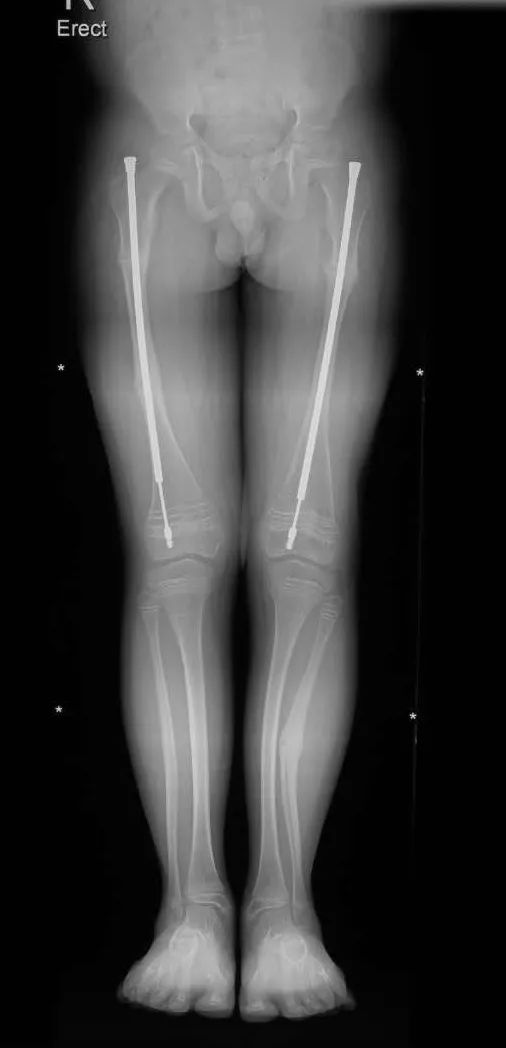

16 岁那年,云辉陆续动了 2 次手术,在体内植入髓内钉,骨头的弯曲和易折得到改善,手术恢复之后,他终于有机会回归校园,直接进入了一所高中,而他自学的基础,也让他不至于在高中落后于人。

髓内钉的示意图